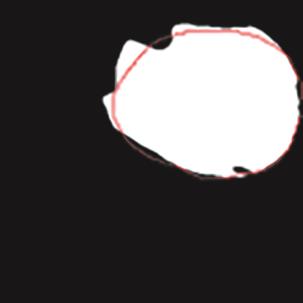

乳腺癌是全球女性最常见的恶性肿瘤之一,准确的病变分割对于乳腺癌的早期诊断与治疗具有重要意义。然而,由于病变形态的多样性以及超声成像机制的复杂性,现有基于深度学习的乳腺超声图像病变分割方法在分割准确性方面仍面临巨大挑战。为进一步提升乳腺超声图像中病变区域的分割精度,该文基于经典U-Net架构,提出了一种新型乳腺超声图像病变分割网络(CWSASKM-BBAM-Net)。首先,在网络中引入逐通道空间自适应选择核卷积模块(CWSASKM),根据不同通道的语义特征为每个空间位置自适应选择感受野大小,以增强多尺度信息的建模能力;然后,引入双向边界感知机制(BBAM),通过融合正向与反向注意力,对目标显著区域及其边界进行协同建模,同时逐步提升对非显著区域与病变区域的区分能力,以进一步强化边界信息的表达;最后,在3组公开乳腺超声图像数据集(BUSI、UDIAT和STU)上开展分割实验。结果表明:该方法在数据集BUSI上的杰卡德指数、精确率、召回率和Dice相似系数分别为71.97%、82.85%、81.40%和80.44%,较次优方法分别提升1.69、1.05、1.28和1.84个百分点;在数据集UDIAT上,这4项指标分别达到78.14%、88.31%、86.73%和86.10%,较次优方法分别提升了2.75、2.04、0.56和2.01个百分点;在外部数据集STU上,该方法也取得了优于其他方法的整体表现。实验结果表明,CWSASKM-BBAM-Net在乳腺超声图像分割任务中展现出更优的整体性能。